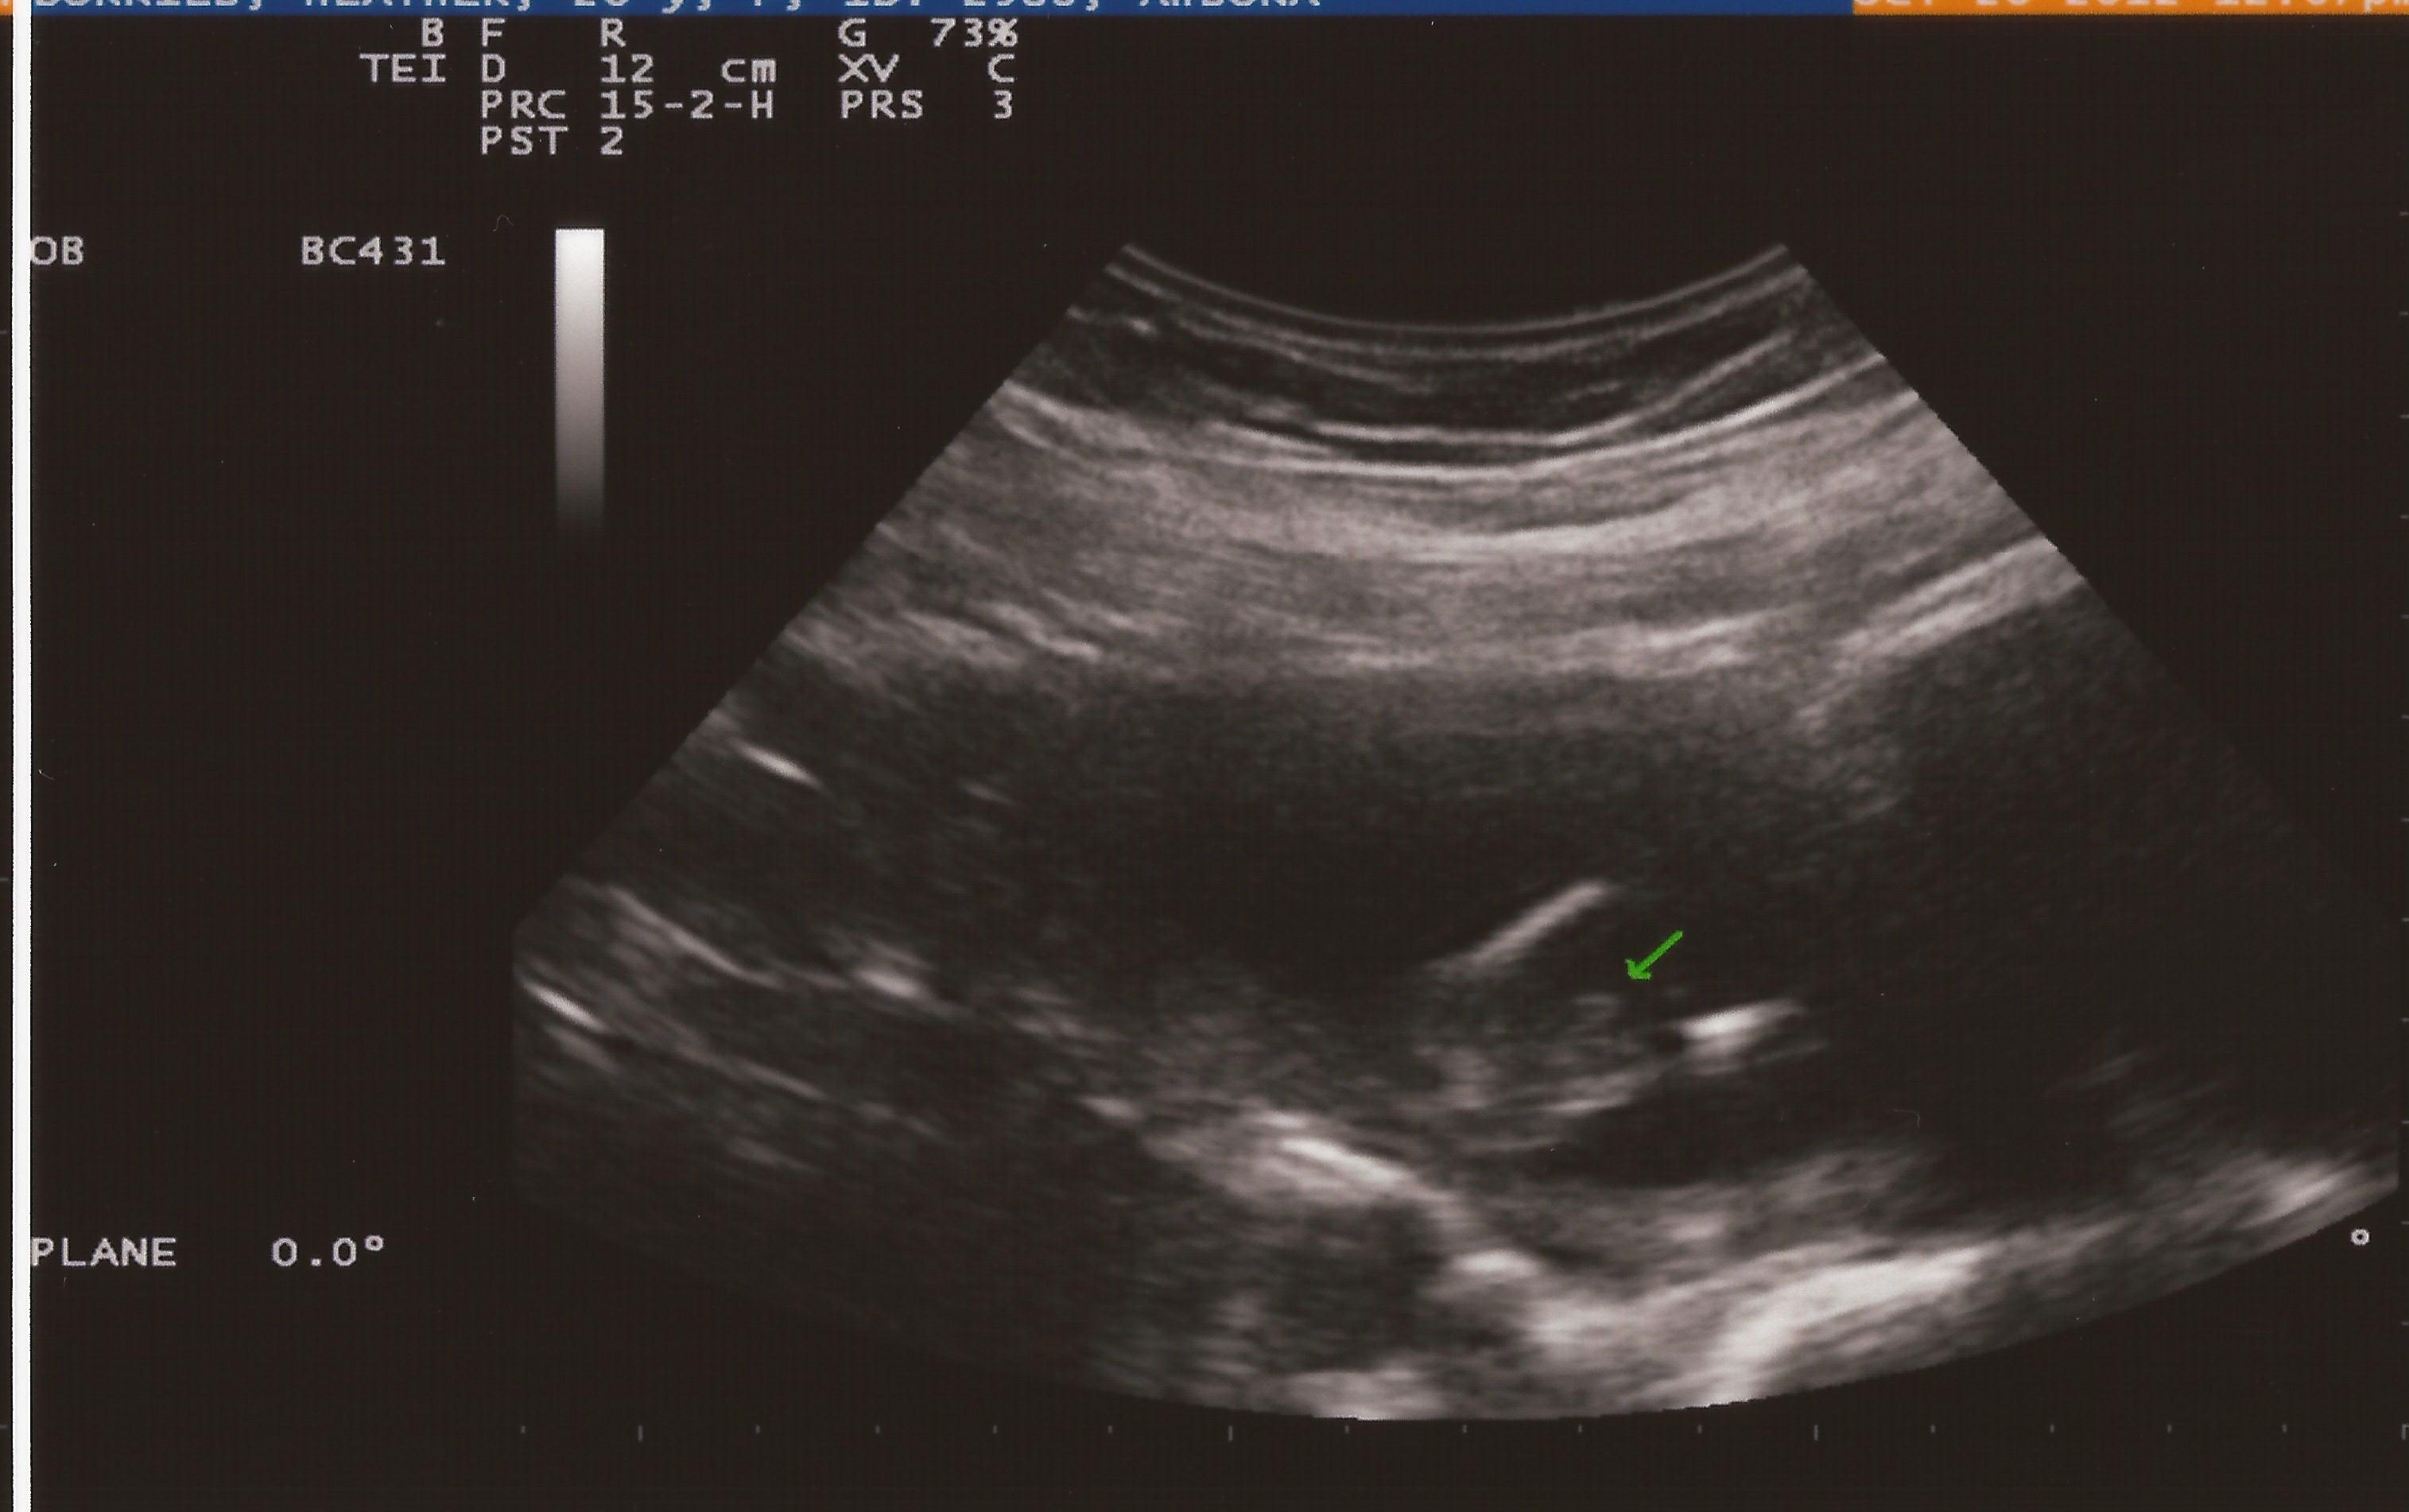

Attachment 5658Attachment 5657

So I am going next week for an actual gender check ultrasound but today the tech went poking around to see what she could find. Well she found confusion... one pic looks girly and one looks possibly boy (she did say it could be umbilical cord) - she wouldn't give me an opinion. What is yours?